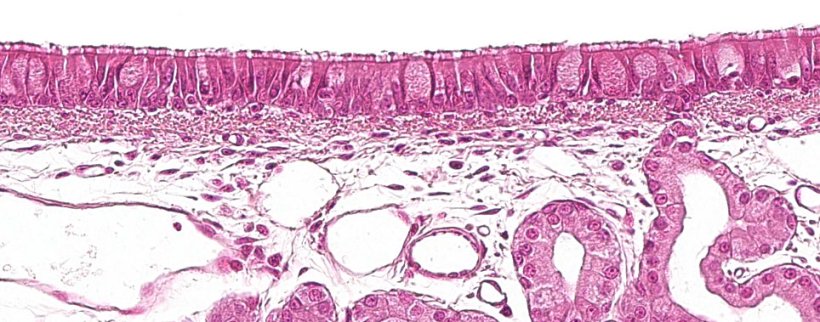

A primeira parte do sistema respiratório, a porção condutora ou vias aéreas, vai da cavidade nasal até às últimas ramificações dos bronquíolos, e também inclui os seios nasais e paranasais que estão conectados à cavidade nasal, nasofaringe e laringe. Todas estas estruturas tubulares estão revestidas por um epitélio pseudo-estratificado ciliado com células caliciformes (figura 1), responsável por um dos principais sistemas de defesa da mucosa respiratória, o aparelho mucociliar. Este sistema é composto pelos cílios das células do epitélio respiratório, junto com as secreções das células caliciformes e as glândulas seromucosas que aparecem sob a mucosa respiratória e a sua principal função é eliminar as partículas que entram através do ar inspirado. As glândulas segregam um líquido claro, de baixa viscosidade e rico em proteínas, que se dispõe entre os cílios, formando um meio que favorece seu movimento para cima. O muco segregado pelas células caliciformes é depositado nos cílios e permite a aderência das partículas inaladas. O movimento ascendente dos cílios empurra o muco em direção à parte superior do sistema respiratório, que pode ser engolido e passado para o sistema digestivo, onde é digerido, ou expelido para fora pela boca e/ou cavidade nasal. Agentes como Mycoplasma hyopneumoniae, que provoca a perda dos cílios, ou vírus como Influenza suína ou o coronavírus respiratório, que provocam a destruição das células epiteliais, destruindo este sistema de defesa.